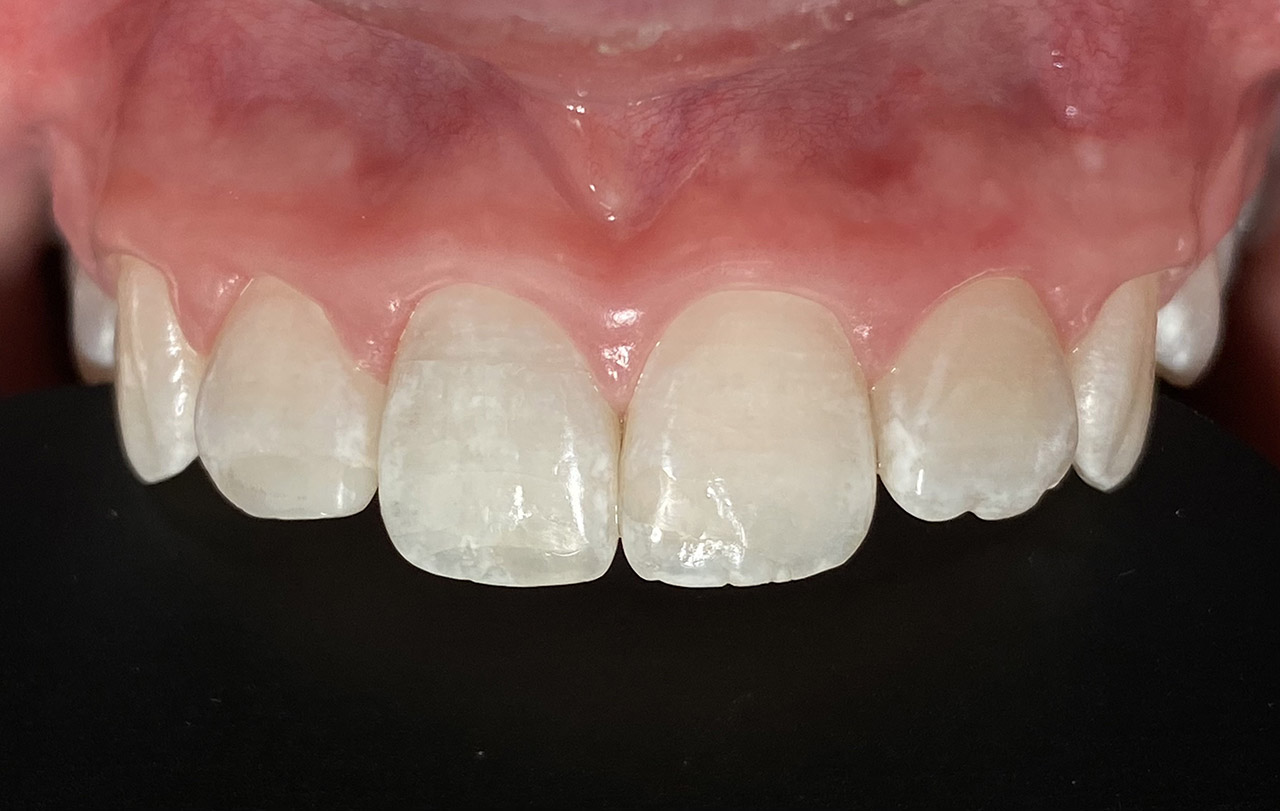

Parodontologie/Gingivahyperplasie:

Diagnose: Gingivahyperplasie durch Medikamente (Blutdrucksenker), unzureichende/nicht mehr mögliche Mundhygiene und überstehende Füllungen.

Therapie: Gingivektomie und anfinieren der Füllungen. Letztes Foto 1 Woche postOP.